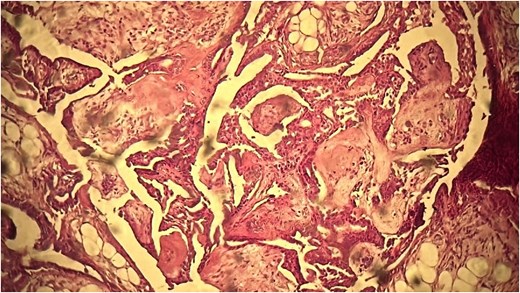

A 53-year-old Moroccan man, with no significant medical history, presented with a cheek swelling evolving over 6 months without associated symptoms. Clinical examination revealed a 1.7 cm cystic-like swelling in the cheek, suggestive of a ruptured epidermoid cyst. It was mobile and skin-colored, without inflammatory signs. Lymph nodes and salivary glands were normal. An excisional biopsy of the mass was performed. Macroscopically, it was a 1.7 cm beige, friable to firm, rounded nodule. Microscopic examination showed a well-circumscribed benign tumor proliferation composed of cysts, tubules, and ducts (Fig. 2), lined by a bilayered epithelium. The cells exhibited no nuclear atypia (Fig. 3). The fibromyxoid and chondroid stroma allowed for diagnosis without additional techniques. There was no perineural invasion or vascular emboli, and surgical margins were clear. Postoperative recovery was uneventful, and no further follow-up or additional examinations were necessary.

Benign tumor proliferation composed of cysts, tubules, and ducts.